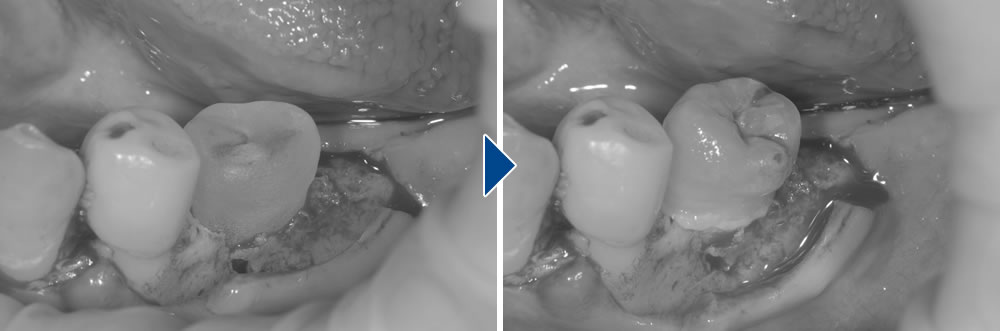

こちらは、保存不可能な歯を抜歯後に親知らずを移植して咬み合わせを改善した症例です。

抜歯・即時移植

形が決まったら、抜歯して即時移植します。